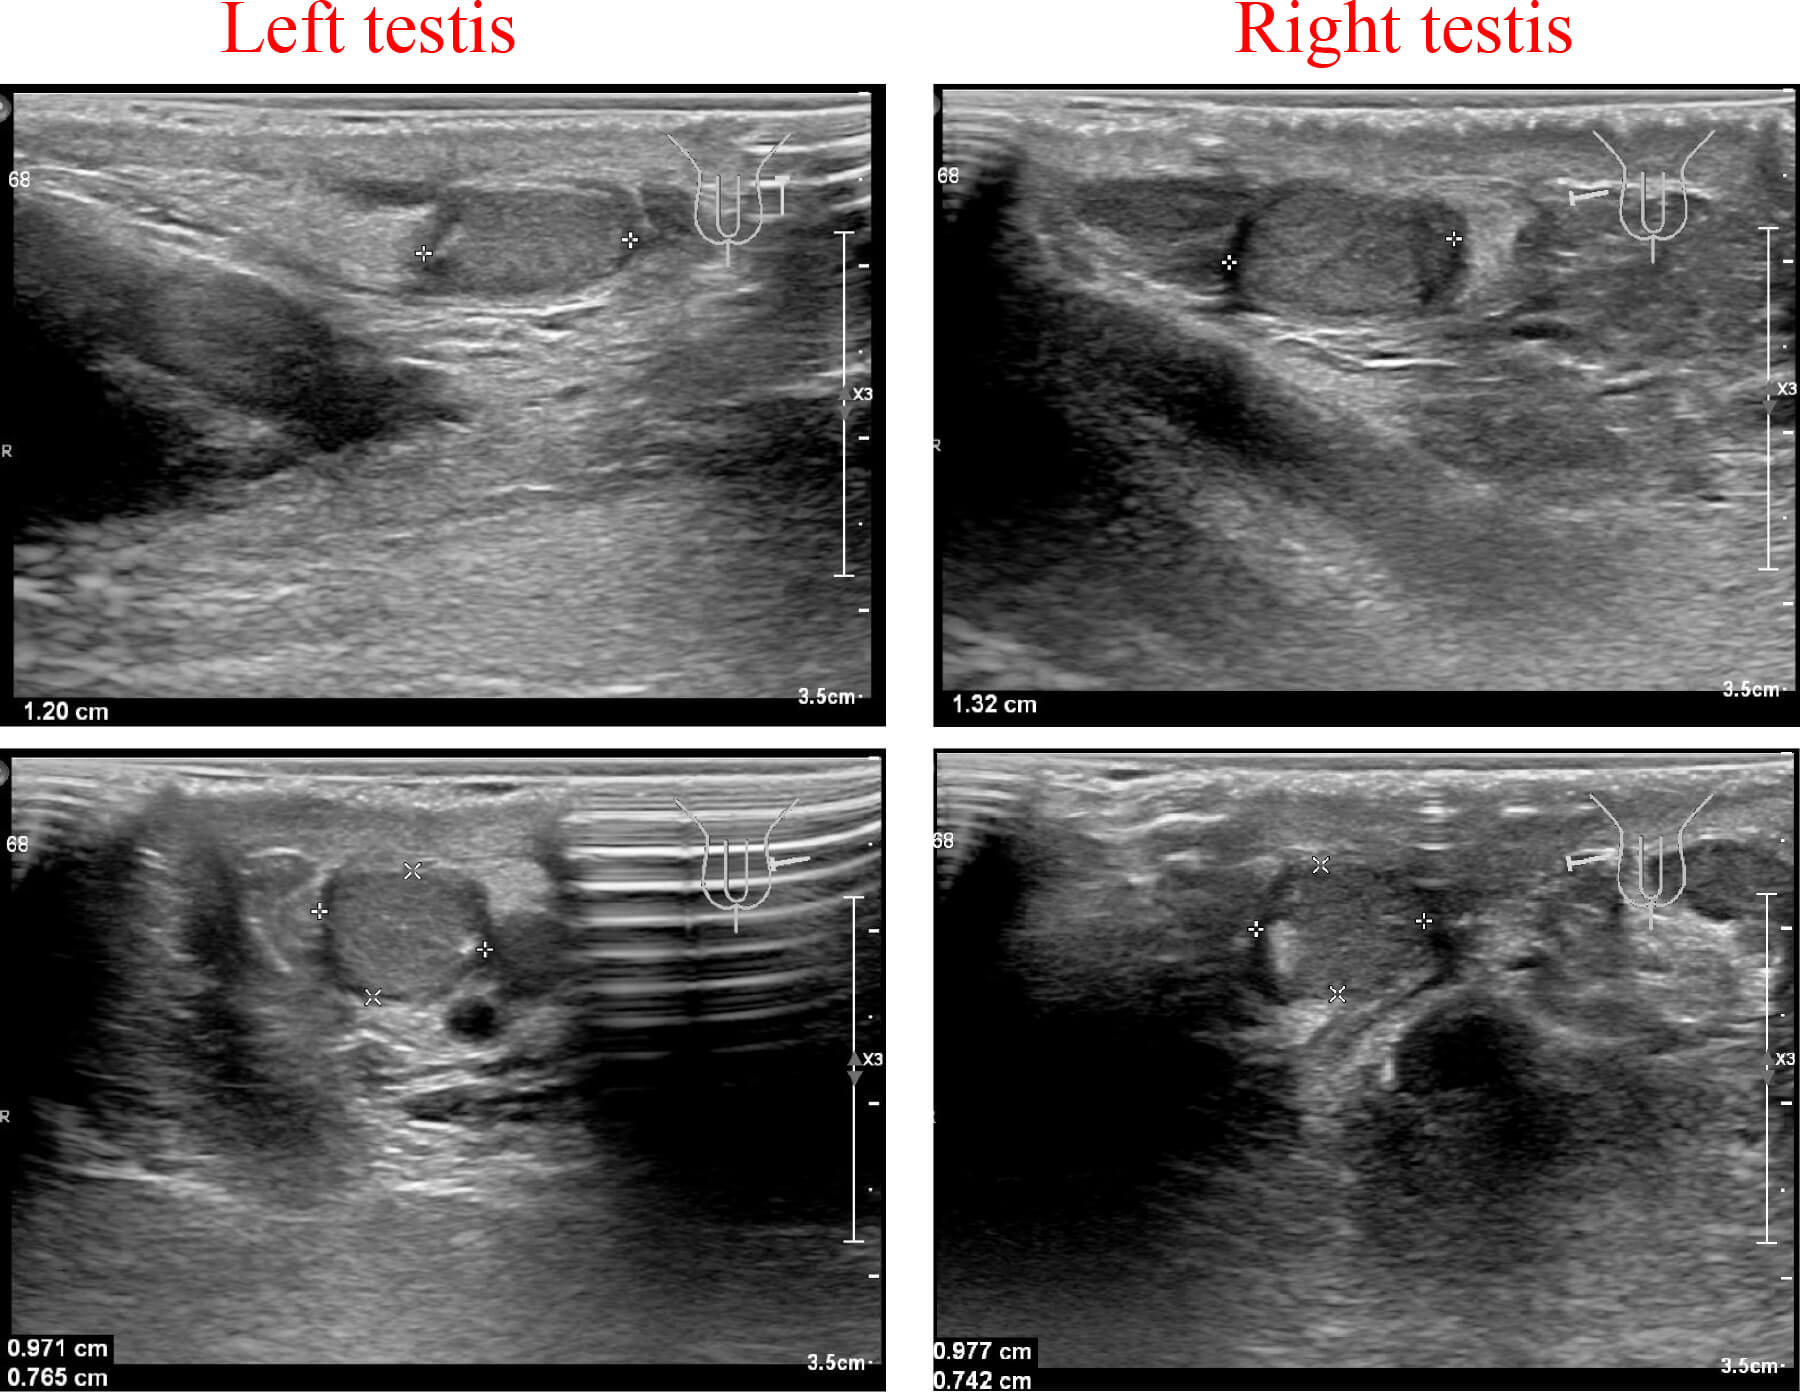

In 56-year-old males, normal testicular dimensions are generally in the range of

32–50

Fig. 2.

Testicular ultrasound report of the patient. Ultrasound examination showed bilateral testicular atrophy.